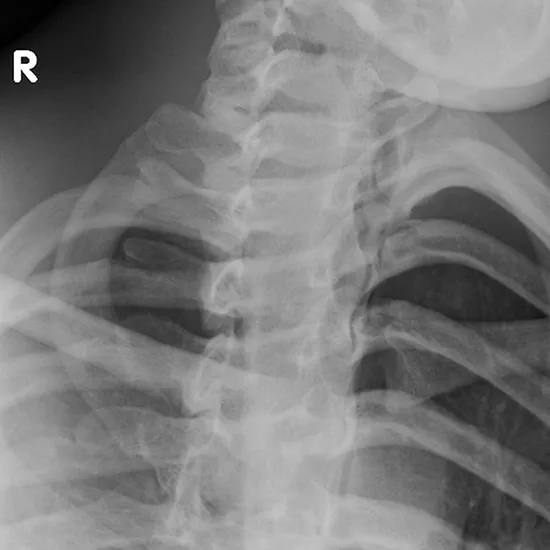

X-ray Sternoclavicular Joint Right View

A sternoclavicular joint X-ray is used to see the region at the base of the neck where the collar bone connects to the breastbone and the first rib. It is also helpful to see the surrounding soft tissues (skin and muscles).